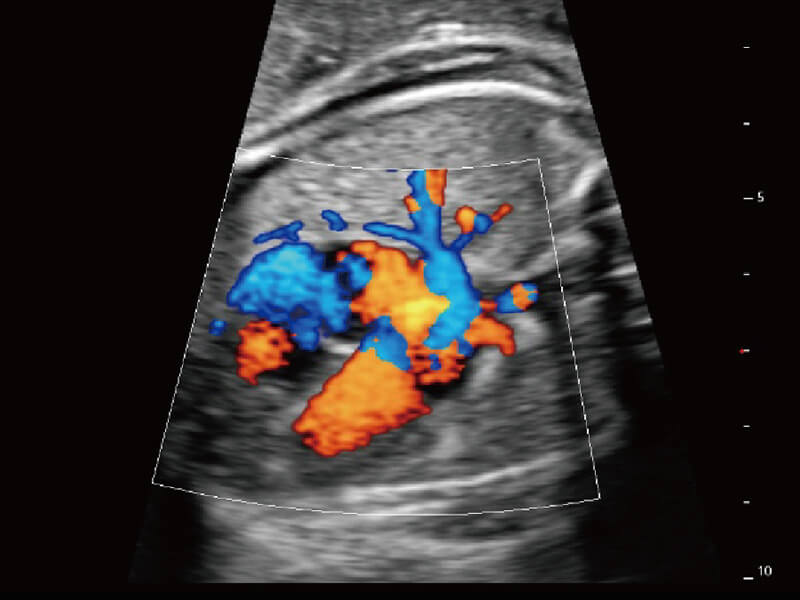

彩色多普勒超声诊断系统